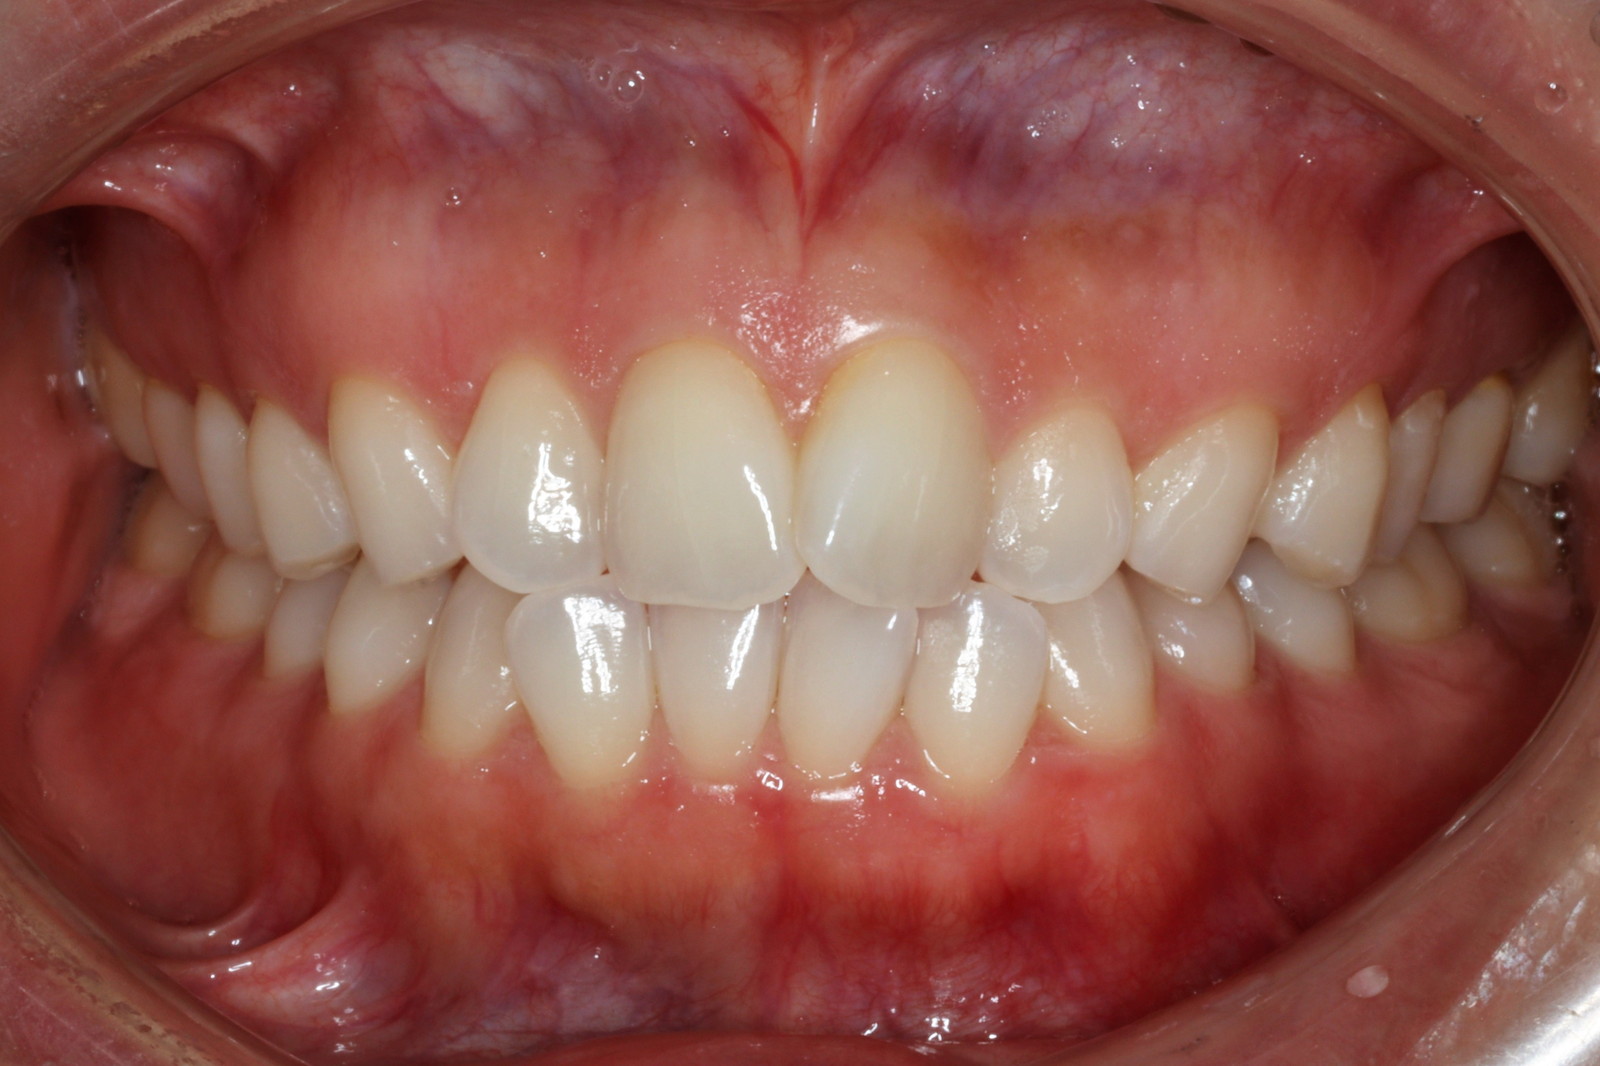

問診を行い、お口の悩みや希望を確認します。レントゲン撮影や口腔内写真の撮影など、必要に応じた精密検査を行います。